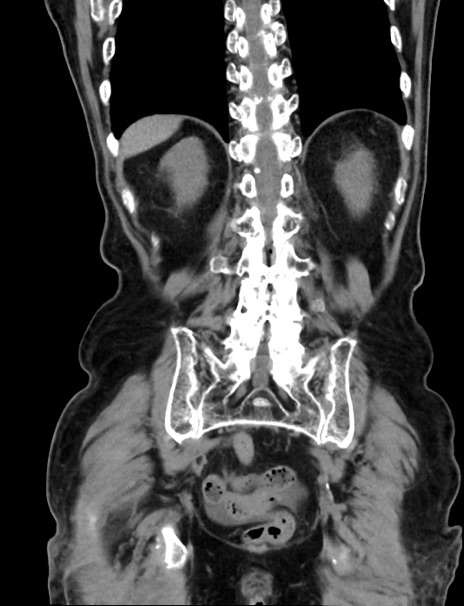

症例33(冠状断像)

【症例】70歳代 女性

【主訴】心窩部痛

【現病歴】延髄病変の精査・加療にて神経内科入院中。本日より心窩部痛あり。

【既往歴】虫垂炎

【身体所見】右下腹部を中心に圧痛と反跳痛あり。

【データ】WBC 10900、CRP 0.02